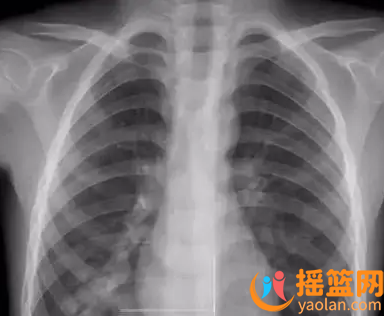

有人可能會擔心,在胸透后能否安全地考慮要孩子呢?

其實,在胸透后的3個月內是完全可以考慮要寶寶的。這是因為女性每個月都會排出卵子,并且卵子能夠存活48小時左右。所以,在經過專業研究和實踐驗證之后,專家們認為在胸透后3個月內懷孕是安全可靠的。

現代X線設備具有低輻射和高分辨率的特點。這意味著做完胸透后不會對懷孕產生負面影響。科技進步讓我們更加放心地繼續懷孕和追求自己的夢想。

根據專家意見,在完成胸透后半個月左右考慮要孩子或者等待三個月再迎接寶寶,能更加安全保障胎兒健康。這樣做不僅能確保卵子質量,還能避免對未來寶寶產生任何影響。

此外,請放心使用現代X線設備進行檢查。現代X線設備射線量低且分辨率高,給您提供了更加安全保障您和您未來寶寶健康的機會。

對于女性來說,在完成胸透后至少需要等待3個月才能懷孕。此外還需要注意補充營養并進行常規的孕前檢查。

對于男性來說,在完成胸透后建議至少再等待半個月才考慮要孩子。